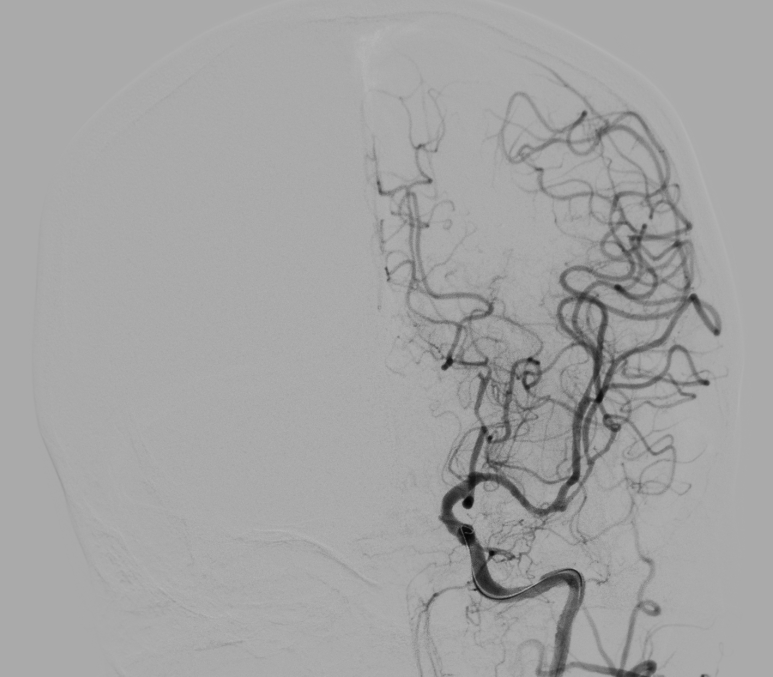

10 分钟后,手术顺利完成,堵塞血管成功开通,濒临坏死的脑细胞被及时 “救回”,张女士的病情得到了有效控制。

而取栓手术,就是医生通过微创的方式,直接把堵在血管里的血栓取出来,快速打通被堵塞的 “生命河道”,拯救濒临死亡的脑细胞。

取栓技术是近年来脑梗死治疗领域的革命性突破,让无数原本可能重度残疾甚至死亡的患者重获新生。